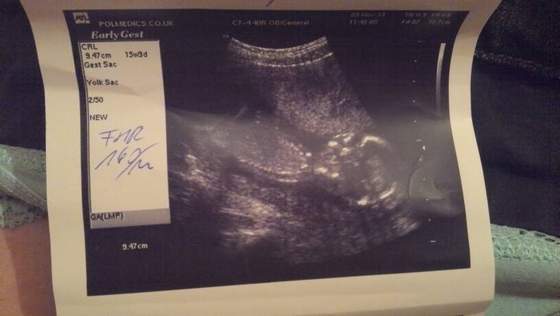

widac siusiaka ;))) miedzy udem a lydka